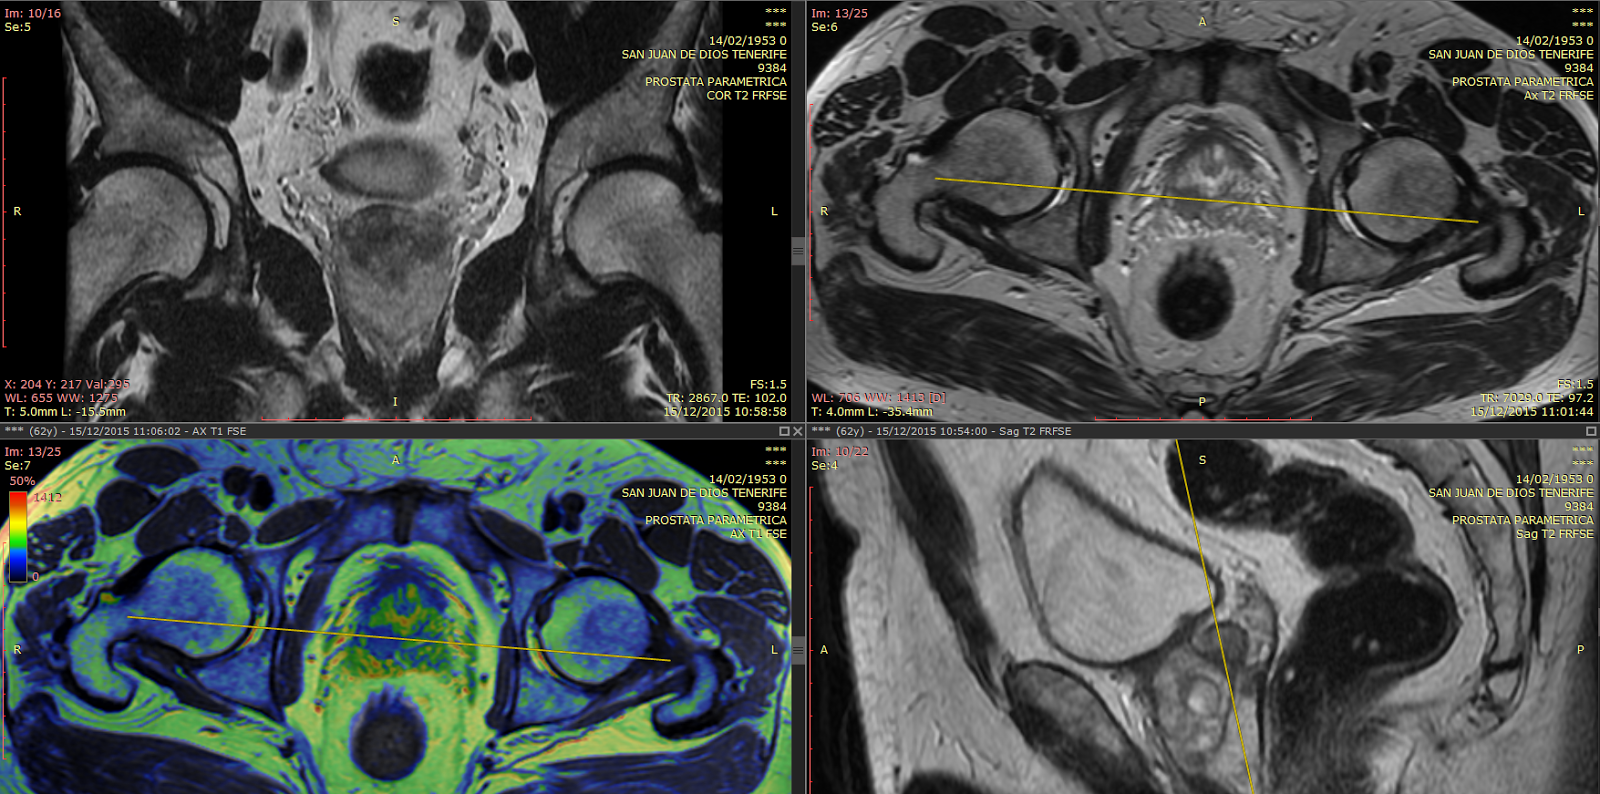

Como Se Hace Una Resonancia De Prostata, , , , , , , 0, Resonancia Multiparamétrica de Próstata, todo lo que debes saber - Sedimed, sedimed.com.pe, 1500 x 787, jpeg, Web¿Cómo se hace una resonancia magnética de próstata? El médico inserta la antena por una distancia corta adentro del recto. La RMN de la próstata no utiliza. WebLa Resonancia Magnética multiparamétrica (RMm) de la próstata consiste en la práctica de una secuencia morfológica T2 (define la forma, tamaño y límites de la., 20, como-se-hace-una-resonancia-de-prostata, Novedades y Muebles Web¿Cómo se hace una resonancia magnética de próstata? El médico inserta la antena por una distancia corta adentro del recto. La RMN de la próstata no utiliza. WebLa Resonancia Magnética multiparamétrica (RMm) de la próstata consiste en la práctica de una secuencia morfológica T2 (define la forma, tamaño y límites de la.

WebLa resonancia magnética multiparamétrica de la próstata es una prueba radiológica que nos proporciona información sobre la forma y señal de la próstata en sus. WebRESONANCIA MAGNÉTICA DE PRÓSTATA Lea cuidadosamente y siga estas recomendaciones como preparación para el examen. Asistir a la sede de atención 30. WebEl objetivo de la RESONANCIA DE PRÓSTATA es visualizar el contenido y estructura del tejido prostático y poder determinar si presenta zonas de inflamación, tumoraciones (ya. WebResonancia magnética multiparamétrica de próstata. La resonancia magnética multiparamétrica de próstata consiste en tomar distintas secuencias de. WebPara prepararte para la biopsia de próstata, el urólogo te pedirá: Una muestra de orina para determinar si tienes infección urinaria. Si tienes infección de las. WebEl médico introduce rápidamente una aguja fina y hueca en la próstata. Esto se hace a través de la pared del recto (biopsia transrectal) o a través de la piel entre el. WebUna resonancia magnética es una prueba diagnóstica no invasiva que permite a los especialistas detectar la presencia de enfermedades y patologías en el. WebLa Resonancia Multiparamétrica de próstata proporciona una imagen morfológica detallada de alta resolución que sirve de mapa y guía para dirigir la biopsia, si es.